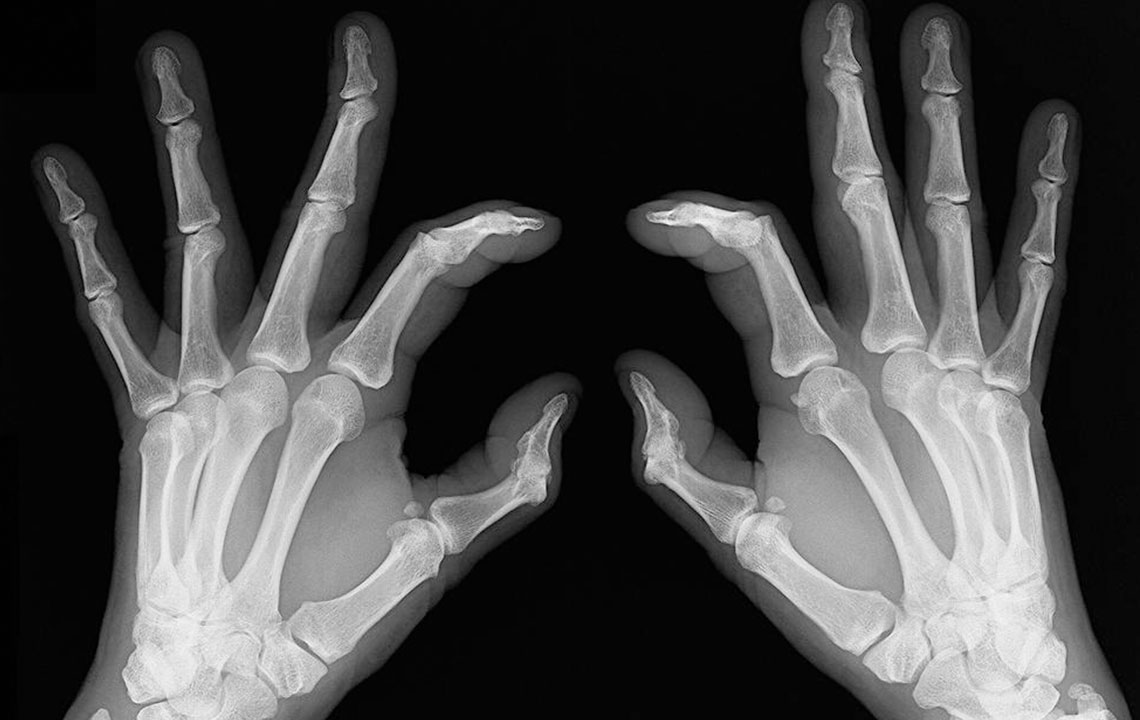

People who have rheumatoid arthritis often wake-up early in the morning complaining of stiff joints and restricted movement. The mobility is back slowly and with little joint movements .   Joint redness: Sometimes the troubled area also experiences redness and feels warm to the touch. However, make sure the redness is not due to reasons such as a bruise or a scrape of the skin.   Bone deformation: Arthritis also attacks the bones and makes them crooked and stiff. Look out for signs of any subtle changes in your joints and test them for pain levels.